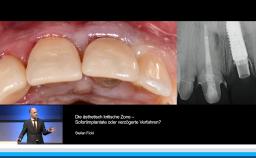

Prof. Buser berichtet in dieser Präsentation, die im Rahmen des Deutschen ITI Kongresses in Dresden im Jahr 2015 gehalten wurde. Langzeiterfolg von Implantaten über 20 Jahre, über den optimalen Implantation und Belastungszeitpunkt. Zunächst erläutert er die gewandelte Altersstruktur der Implantatpatienten und definiert die primären und sekundären Behandlungsziele in der Implantologie. Ein zentraler Aspekt der Präsentation stellt die Wahl des idealen Implantationszeitpunktes nach Extraktion mit Focus auf die verzögerte Sofortimplantation in Verbindung mit GBR dar, die auch mit einem informativen OP Video unterlegt ist. Er setzt sich kritisch mit dem Konzept der Sofortimplantologie auseinander und stellt die Ergebnisse der letzten ITI Konsensuskonferenz dar. Er definiert die Belastungszeitpunkte auf der Basis der ITI Konsensuskonferenz. In einem zweiten Schritt wird die Planung der Belastung in den Zusammenhang mit der Verlaufsbeurteilung der Implantatstabilität mittels ISQ Messung gestellt. Am Beispiel des Sinuslift mit primärer Implantation wird abschließend das Konzept eines flexiblen Belastungszeitpunktes auf Basis der ISQ Messung diskutiert.

• die Wahl des idealen Implantationszeitpunktes in der ästhetisch kritischen Zone verstehen